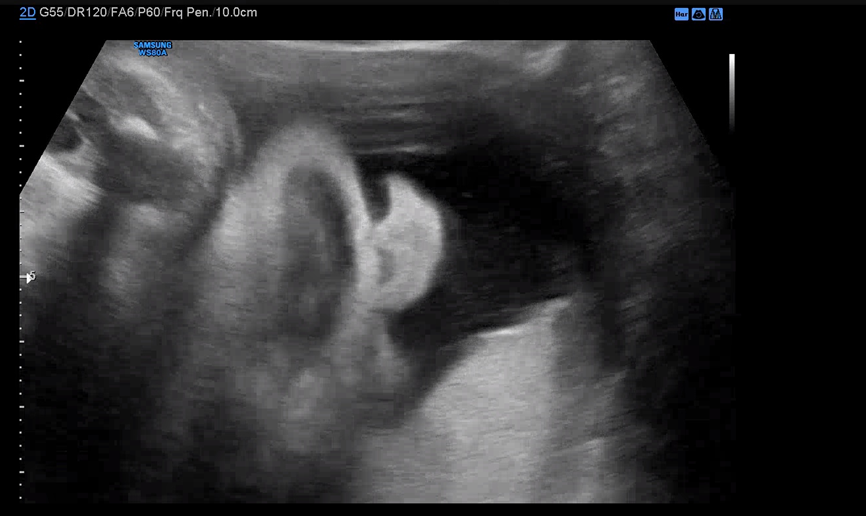

막달 검사를 마치고 30분 정도 대기한 뒤 원장을 진료를 봤다. 4분가량 배 초음파로 아기의 상태를 체크해주시는데 BPD, Fetal HR, AC, FL 순서로 봐주시고 마지막으로 아기 얼굴을 보여주셨다.

항상 이 시간에 자고 있는 우리 아기. 이번엔 초콜릿 우유를 먹지 않아서 그런지 얌전히 자고 있었다.

이제 점점 자궁이 좁아 불편할 텐데 그래도 얌전히 잘 버텨주고 있어 대견하다. 태동은 매일 느끼지만 내 기준 엄청 아프지 않은 것 같다.

자면서도 입은 오물오물.